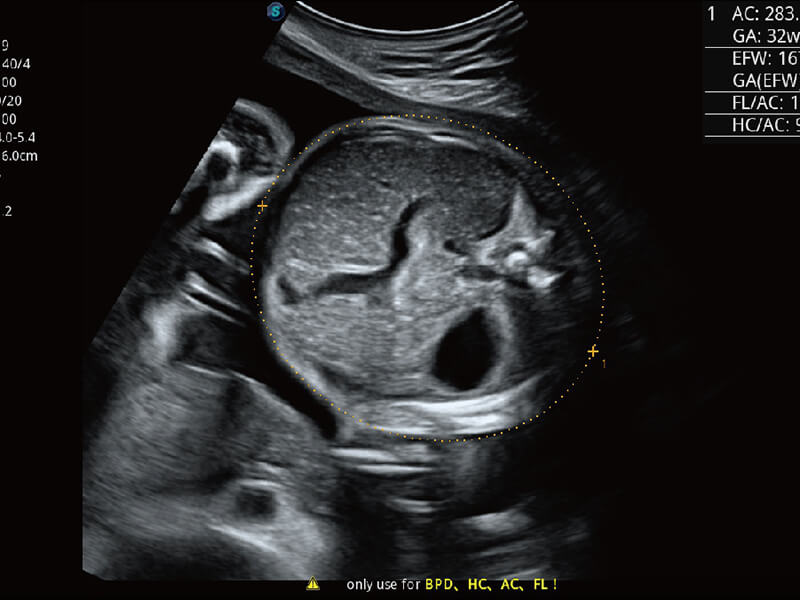

性能优异的硬件架构,极大提升超声系统的运行效率和数据处理能力。相比以往超声成像系统,Wis+平台为您带来极快的响应速度和成像帧频,提升检查流畅度。

S60探头工艺,从前端信号处理每一个环节采集无损声学数据,真实还原组织原貌,再现解剖细节。

超宽频带技术,为容积成像带来优质的二维图像基础,为您呈现丰富的结构细节,栩栩如生地展示宝宝的宫内形态以及各种组织的立体结构。